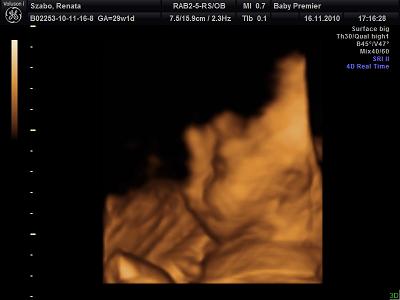

Itt csukva volt a szeme!

Ez meg a szép mosoly,profilból!